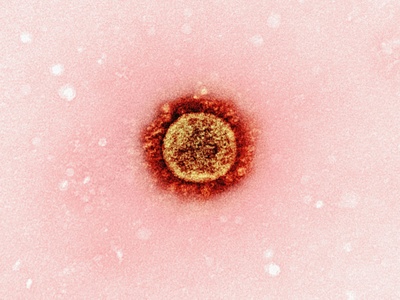

COVID-19

COVID-19 is caused by SARS-CoV-2, commonly producing fever, cough, fatigue and loss of smell; severe cases cause pneumonia and long-term symptoms. Global since 2019; spreads by respiratory routes. Vaccines and masks reduce risk; treatments and antivirals available for high-risk patients.